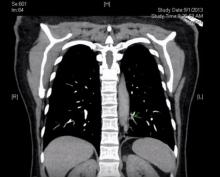

This video shows a VATS resection of pulmonary sequestration in a previously healthy 55-year-old woman, who presented with chest pain. Pulmonary sequestration is a rare congenital abnormality of the lung consisting of nonfunctioning lung tissue that does not have normal communication with the tracheobronchial tree or pulmonary arteries. The lung receives its blood supply from the systemic circulation. The prevalence of sequestration is 0.15-1.8% of the general population (1).

The clinical presentation of pulmonary sequestration can be variable. Many cases are found on routine prenatal ultrasound and affected newborns are asymptomatic. If symptomatic, neonates present with respiratory distress (1). Intralobar sequestration usually presents later in life with recurrent pulmonary infections. Often, sequestration is found incidentally on chest radiographs (2). Once identified, further imaging such as a CT or MRI can be done to characterize the lesion and localize the vasculature (1).